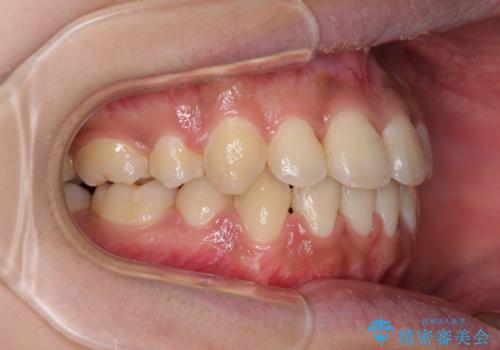

- 八重歯と上下前歯のでこぼこを気にして来院された患者様です。

上下前歯部叢生のスペース獲得のため、上下顎左右小臼歯各1歯(計4本)と全ての親知らずを抜歯して、矯正治療を行うこととしました。

上下の正中位置が大きくずれていたため、治療期間の長期化や正中が合わないまま終了することが予想されましたが、思っていた以上にスムーズに歯が移動し、満足いただける仕上がりとなりました。